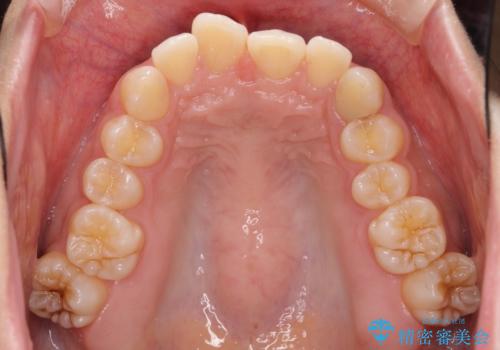

奥歯の倒れた歯を改善 インビザラインでの矯正治療

- 前歯のデコボコと奥歯の不正咬合を気にして来院された患者様です。

左右の大臼歯が全て鋏状咬合(シザーズバイト)になっており、治療が難航することが予想されましたが、インビザラインにより治療を行うこととしました。

最難関と思われたシザーズバイトは比較的短期間で解消されました。

しかし、治療中に2度の出産を経験され、治療期間は長くなってしまいましたが、咬みやすく、清掃しやすい歯列を獲得することができました。